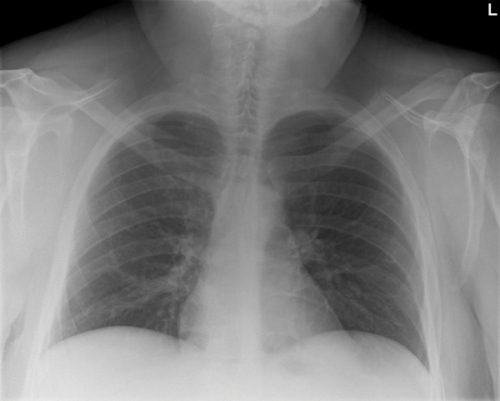

Tool to train medical student's eyes as to what a normal chest x-ray looks like, with over 500 consecutive normal images.